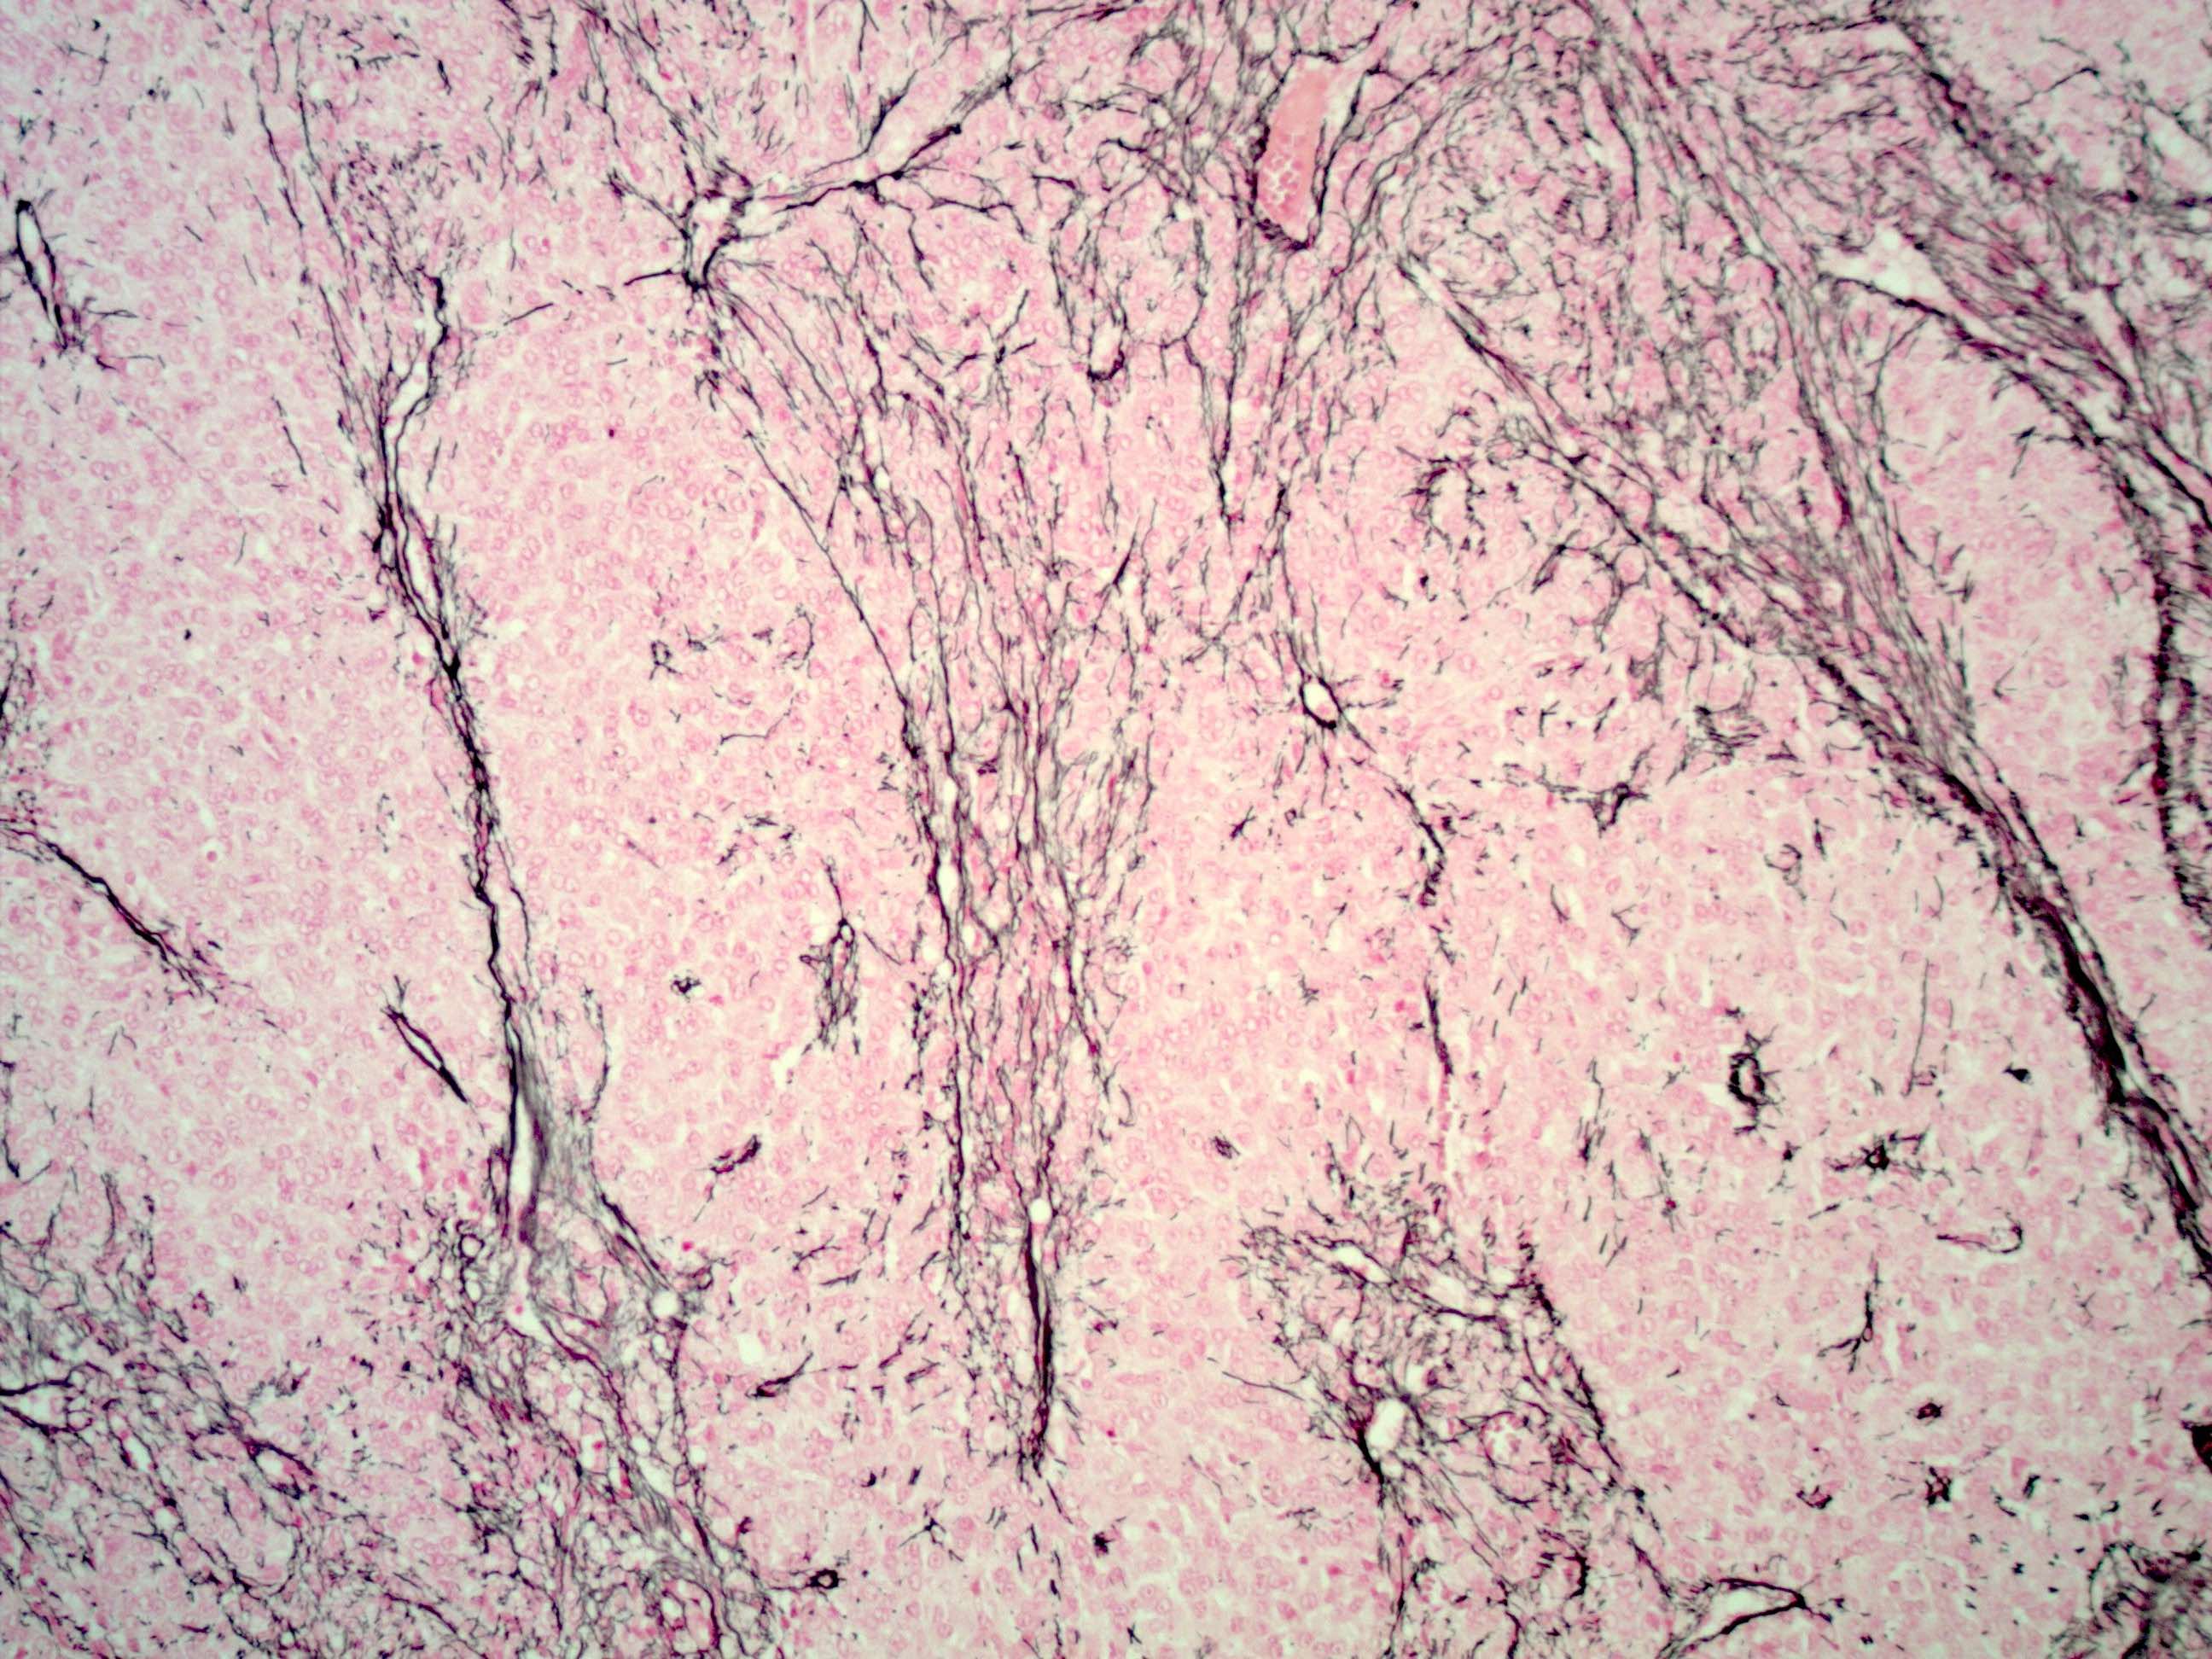

- Reticulin: shows lack of pericellular staining and highlights nests or large groups of granulosa cells and vessels, helps differentiate diffuse pattern from fibrothecoma (Int J Gynecol Pathol 2019;38:143)

Contributed by Shabnam Zarei, M.D. and Sharon Bihlmeyer, M.D.

AFIP images